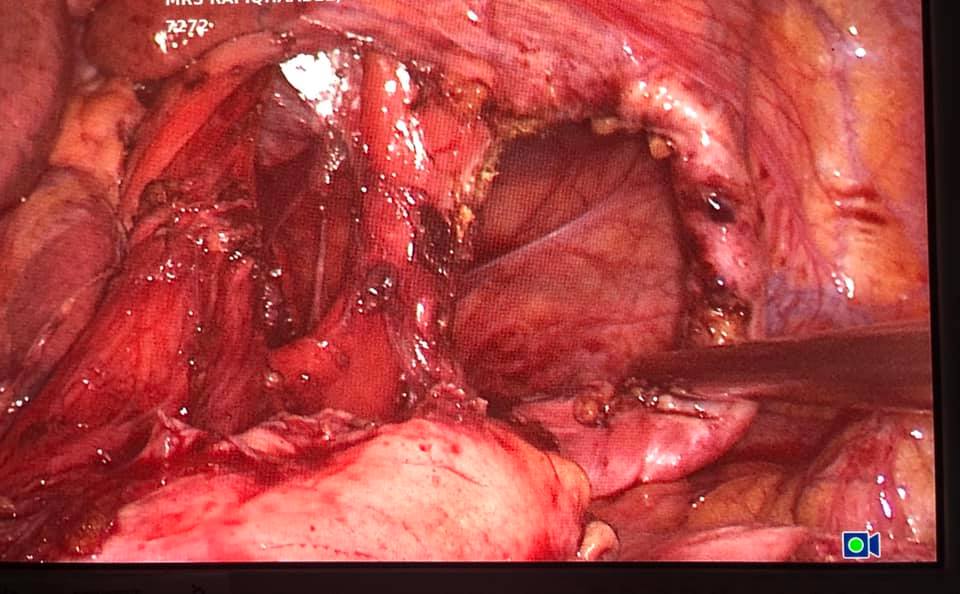

Laparoscopic total proctocolectomy and ileal pouch surgery for ulcerative colitis

Mr SR aged 40 was suffering from steroid resistant ulcerative colitis with severe bloody diahhorea 10-15 times a day with anemia and progressive weight loss not responding to medications. He underwent laparoscopic total proctocolectomy and ileal pouch surgery 2 years ago, performed by Dr. Phani Krishna Ravula. 2 years later on follow up He is now of all medication and cured of ulcerative colitis and back to job with excellent quality of life.